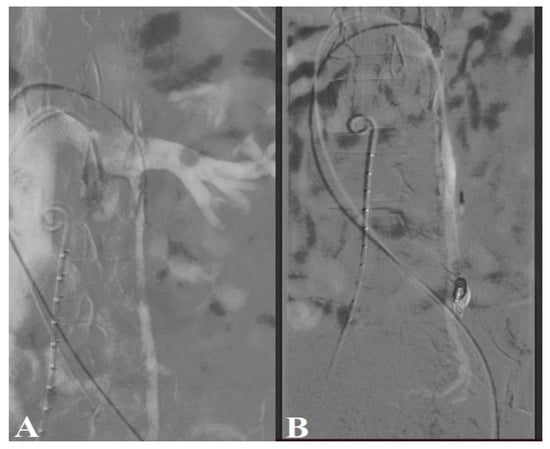

Female Gonadal Venous Insufficiency in a Clinical Presentation Which Suggested an Acute Abdomen—A Case Report and Literature Review